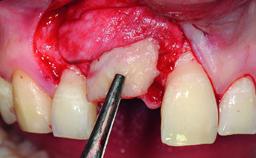

A healthy 28-year-old female patient presented for a consultation on treatment options to restore her upper right central incisor. At the clinical examination, the tooth responded to percussion and palpation. The gingiva was red and slightly swollen, with a mid-facial probing depth of 10 mm. The upper right lateral incisor showed no signs or symptoms, did not respond to exploration and percussion, and the vitality test was positive. The periapical radiograph revealed that tooth 11 had been endodontically treated, with no lesion evident at the apex. A small radiopaque calcified structure surrounded by a narrow radiolucent zone (3 × 3 mm) was present at the apex of tooth 12.